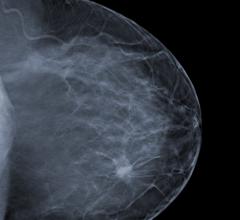

Women's health related to breast imaging, including mammography, breast MRI, ABUS, automated breast ultrasound, breast ultrasound, breast biopsy, PEM and positron emission mammography.

Despite decades of progress in breast imaging, one challenge continues to test even the most skilled radiologists ...